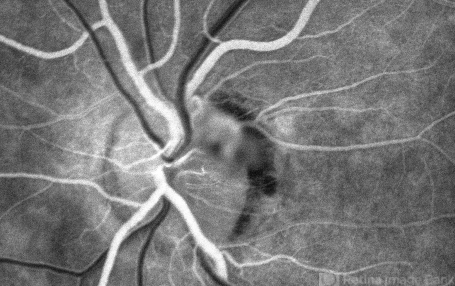

- Unusual presentation of VHL juxtapapillary hemangioblastoma detached from retina with feeder vessels

- Von Hippel-Lindau, retinal hemangioblastoma

FA 26 sec - Description

- 30-year-old female with fhx VHL and CNS hemangioblastomas and visceral lesions. P/C with a floater (no PVD or VH) after episodes of vomiting.